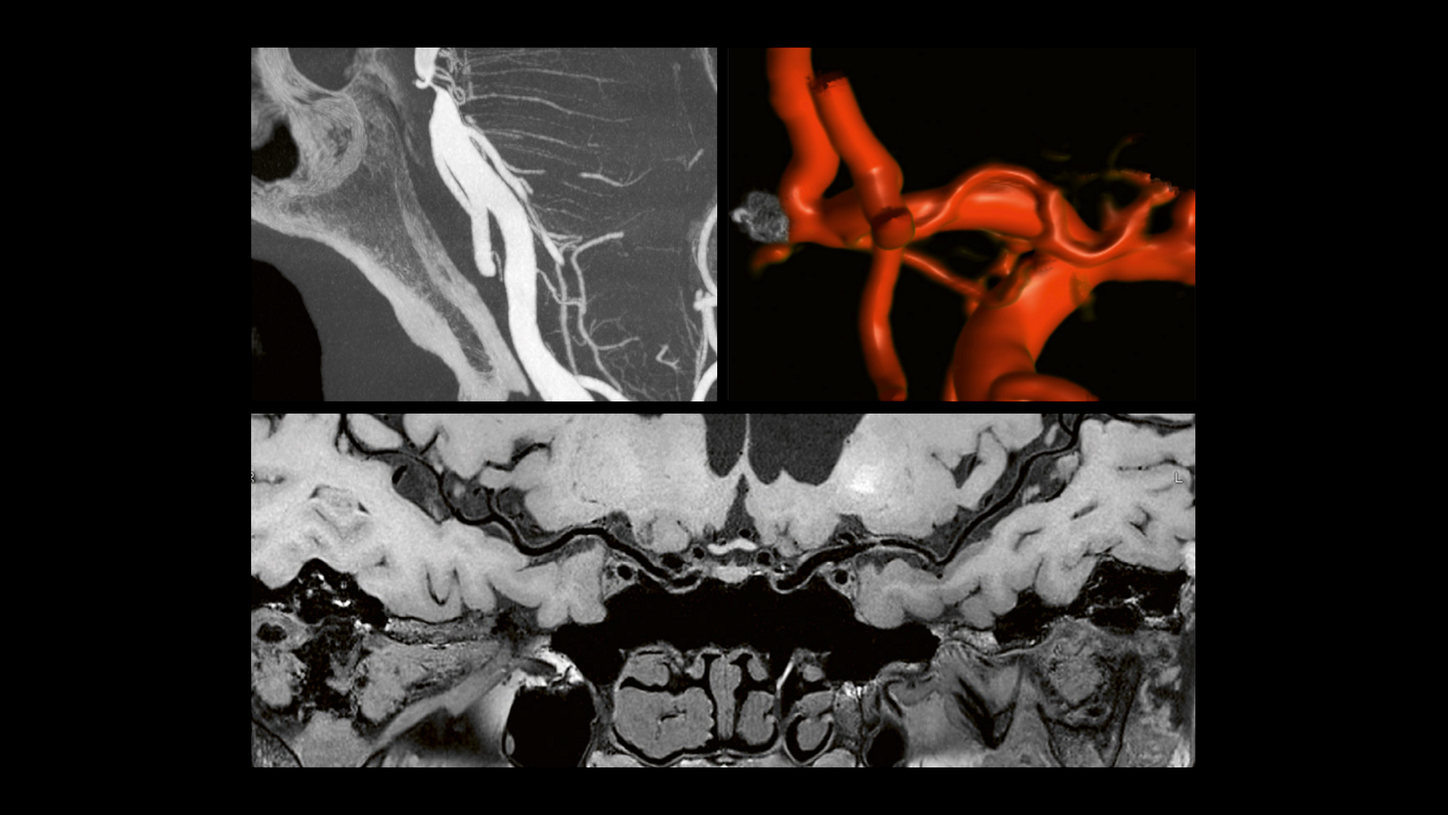

Clear image quality for confident diagnosis and treatment

To quickly and confidently diagnose stroke, assess its impact, and perform mechanical thrombectomy, you need clear information. All our CT and MRI scanners as well as angiography systems let you see even small anatomical details in excellent quality. See for yourself!*

MAGNETOM Vida: Standard stroke protocol

example of hemorrhage visualization

Native syngo DynaCT Sine Spin

syngo DynaCT Sine Spin improves the image quality of cranial Flat-Detector CT (FDCT) scans, especially in the posterior fossa and the basal part of the skull. syngo DynaCT Sine Spin reduces artifacts caused by bony structures.

Native head scan

Assist with or support differential diagnosis of acute stroke with excellent gray-white matter differentiation and contrast enhancement

Perfusion scan

Evaluation of infarct core and penumbra by automatically providing perfusion maps for further treatment decisions

Angiography

CT planning of the following treatment with definition of occlusion length and collateral status and automated bone removal

Cinematic VRT

Clearly visualize clots and get photorealistic and easy-to-understand material for education, publication, and communication

MAGNETOM Sola: T1 contrast sagittal MPRAGE

MAGNETOM Vida: Standard stroke protocol

example of hemorrhage visualization

Native syngo DynaCT Sine Spin

syngo DynaCT Sine Spin improves the image quality of cranial Flat-Detector CT (FDCT) scans, especially in the posterior fossa and the basal part of the skull. syngo DynaCT Sine Spin reduces artifacts caused by bony structures.

Native head scan

Assist with or support differential diagnosis of acute stroke with excellent gray-white matter differentiation and contrast enhancement

Perfusion scan

Evaluation of infarct core and penumbra by automatically providing perfusion maps for further treatment decisions

Angiography

CT planning of the following treatment with definition of occlusion length and collateral status and automated bone removal

Cinematic VRT

Clearly visualize clots and get photorealistic and easy-to-understand material for education, publication, and communication

MAGNETOM Sola: T1 contrast sagittal MPRAGE

MAGNETOM Vida: Standard stroke protocol

example of hemorrhage visualization